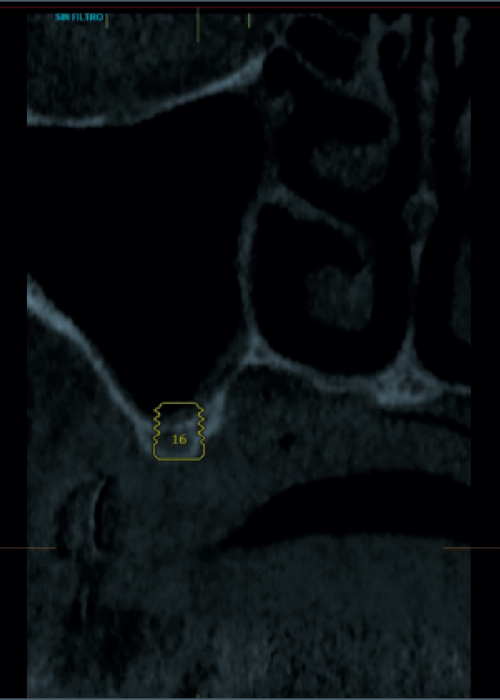

Elevación de seno mediante abordaje transcrestal sin material de relleno con implantes extracortos (5,5 y 6,5 mm). Estudio retrospectivo con un seguimiento de 10 años

Elevación de seno transcrestal con inserción de implantes ultracortos de 4,5 mm de longitud en zonas maxilares posteriores con hueso residual menor o igual a 3 mm de altura

Implantes de 4,5 y 5,5 mm longitud insertados de forma directa en elevación crestal con hueso autólogo unido al Endoret-PRGF en alturas óseas residuales de 2-3 mm: estudio retrospectivo